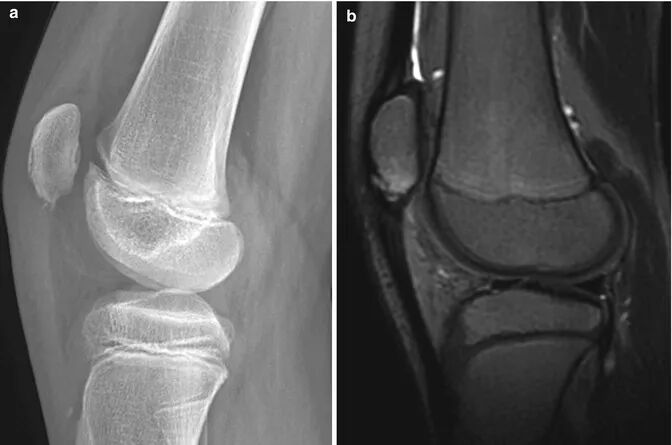

图2 髌骨袖套状撕脱骨折,有两大块骨片从骨性的髌骨下极撕脱。注意髌下脂肪垫(霍法脂肪垫)处伴发的软组织肿胀以及髌腱的增厚情况。

图4 一名患有膝前部疼痛的11岁男孩,患有Sinding-Larsen-Johansson 病。(a)髌骨下极有轻微碎裂。(b)矢状位T2加权脂肪抑制(T2-W FS)图像证实了碎裂情况,并显示出轻度骨髓水肿和髌腱增厚。https://radiologykey.com/the-lower-extremity-congenital-and-developmental-conditions/。